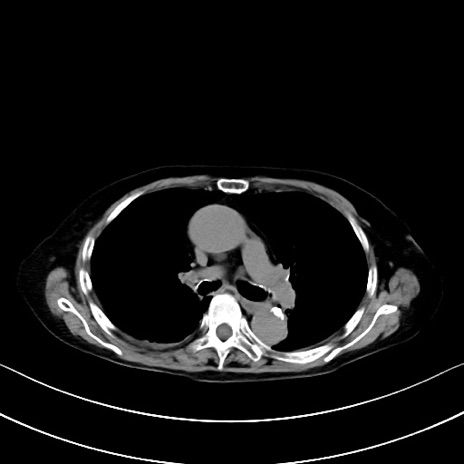

横断像